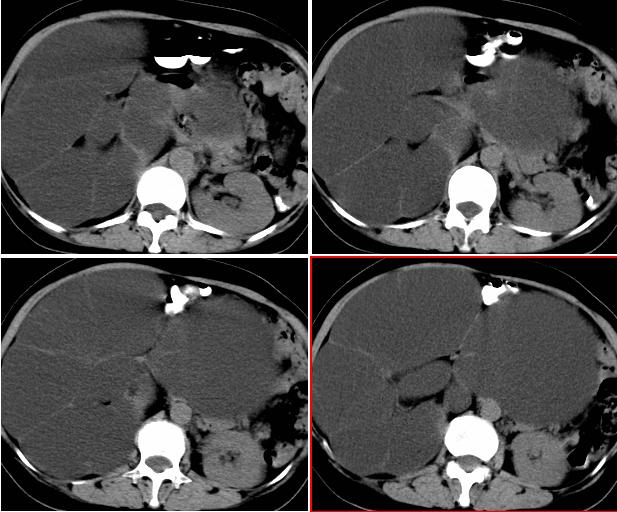

右侧后腹膜巨大囊性肿块影阴,边缘清晰,内见膜状分隔,均匀水样密度,右肾影阴消失,囊块所到区域脏器受挤移位,右侧输尿管扩张,应该考虑:右肾重读积水,巨大肾囊肿不除外。引发肾性高血压。

从囊性低密度区的形态,及分布看我支持1楼战友的分析及诊断意见。{右恻输尿管全程扩张,阻塞位置应该在输尿管与膀胱的交界区,建议行膀胱镜检,楼主还是应该给患者作强化扫描!!!!!}

反推一下:1.那么重的积水,引起积水的原因大部分是右侧输尿管有梗阻,排出受阻。右侧输尿管应该也是重度扩张才对。2.如果是肾积水,而且是右侧输尿管问题引起,那么病人肯定有相应的临床症状:比如输尿管结石引起的血尿、剧痛等症状,至少也会急性发作病史。另,本例显然不需要考虑输尿管癌,膀胱也挺好,更没有无痛性血尿病史。病人8年多没有其他的不舒服,只是腹部日渐膨隆,临床症状显然不支持。3.如果是重度肾积水的话,应该可以看到被压缩的肾皮质,即使很菲薄也多少会有显示的。

右输尿管肾盂肾盏高度括张扭曲,第三狭窄处或周围应见结石或其他原因梗阻。考虑先天畸型,如重复畸形。

右肾明显扩大,皮质菲薄,间隔细,右输尿管全程扩张,右肾重度积水,原因应重点查输尿管膀胱接合处。

右肾重度积水,右输尿管全程扩张,原因待查。做ct增强扫描、重建。